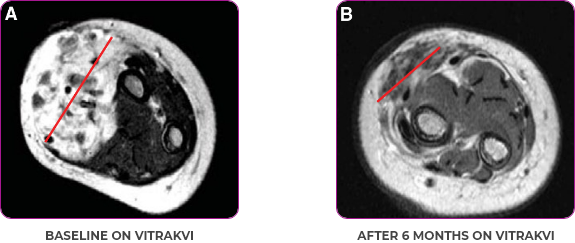

PATIENT CASE:

INFANTILE FIBROSARCOMA

OF SOFT TISSUE1

- 5-month-old with IFSa

- Progression after chemotherapy

- Confirmed PRa after 4 cycles of VITRAKVI® (larotrectinib)

- Referred for definitive limb-sparing surgery after 6 cycles

of VITRAKVI; achieved pCRa,b

VITRAKVI treatment1

- VITRAKVI 100 mg twice daily orally

Response to VITRAKVI1

- Patient achieved a confirmed partial response after 4 cycles of VITRAKVI with a 45% reduction in tumor burden

- Following 6 cycles of VITRAKVI, the patient was referred for definitive limb-sparing surgery

- Pathology revealed a complete pathologic response and clear resection margins with scar tissue noted

Reduction in tumor burden1

MRIa imagery of the brain. Red line indicates the maximum dimension.1

aMRI, magnetic resonance imaging.

Pre- and post-treatment imaging, by DuBois SG et al, is licensed under CC BY 4.0.

aIFS, infantile fibrosarcoma; MRI, magnetic resonance imaging; pCR, pathological complete response; PR, partial response.